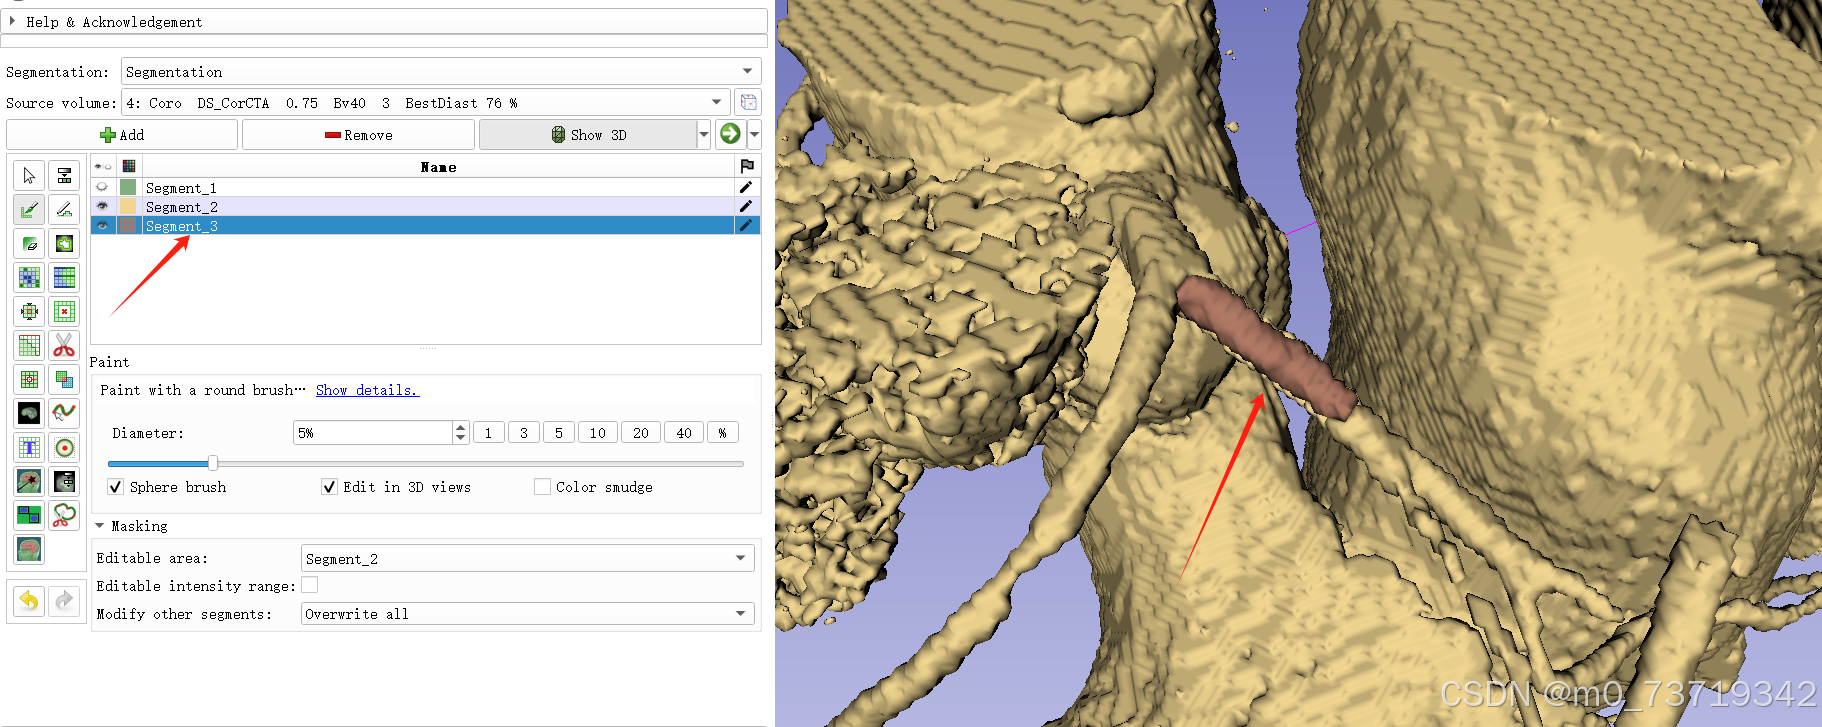

5.三维球刷标出冠脉位置

新建标注3

依次点击如下按钮

在三维视图中拖拉球刷对冠脉进行标注(shift+鼠标滚轮调整球刷大小)

问题:显卡问题使用三维球刷标注卡顿

解决方法1:在标注之前先remove掉三维图像中的小噪点,显卡计算量减小,卡顿减轻